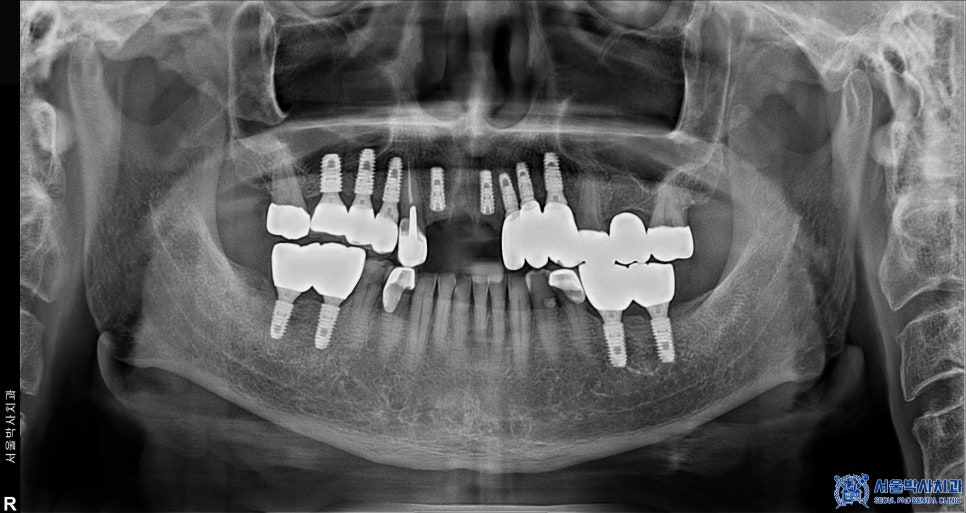

위 환자분은 앞니가 많이 불편해서

임플란트 치료를 고민하고 계셨는데요.

치아를 확인해보니 앞니 두 개는

치아의 뿌리 부분만 남아 있었고,

심한 치주염과 충치로 인해

유지하기 어려운 상태였습니다.

또한, 고혈압과 당뇨 등 만성질환이 있으셔서

치료 진행에 있어 더욱 세심한 접근이 필요했으며,

환자분의 건강 상태를 고려하여 복용 중인

약을 꼼꼼히 확인한 후 치료를

진행하기로 계획하였습니다.